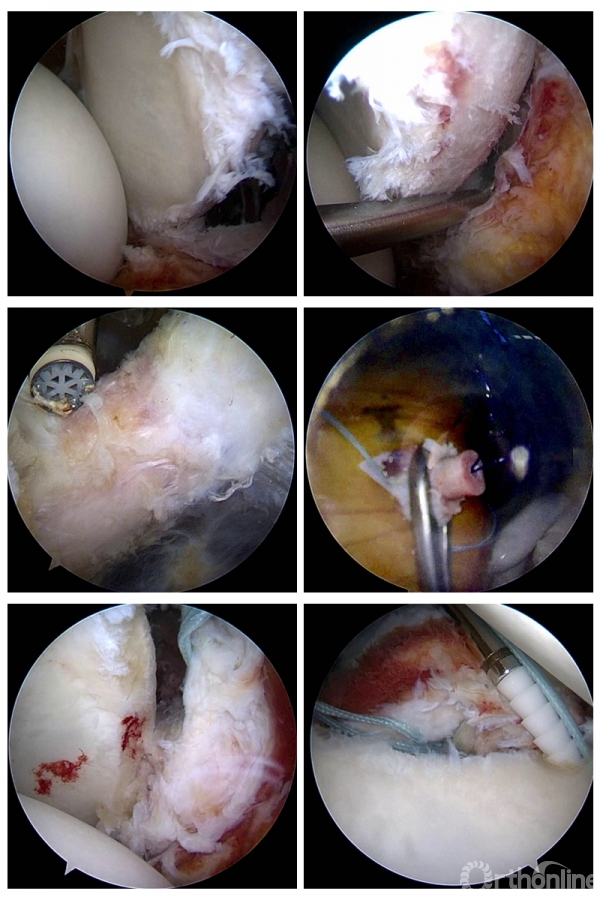

真知灼见,术台见功夫——手术直播

本次会议的重点是手术实时在线直播,在随后的时间里陆续进行。专家们分组轮流进行手术演示。术者根据病情展示各自的独特手术技巧,现场观摩的医生可以即时与术者及其他观摩者交流学术思路,全程互动,有任何疑问随时与术者交流。

在两天的会议中,成功完成了11台手术,包括4台膝关节韧带重建、2台膝关节内侧骨关节炎单髁置换、1台肩关节前方复发性不稳定改良Bristow稳定术,1台巨大肩袖撕裂SCR修补、1台肩肩胛下肌冈上肌撕裂修补、1台跟腱痛风性腱病伴撕裂清理修补、1台距骨骨囊肿关节镜下清理植骨。

△手术名称:左膝前交叉韧带撕裂类等长重建 术者:陈世益教授

△手术名称:肩关节前方复发性不稳定改良Bristow稳定术 术者:崔国庆教授

△手术名称:前后交叉韧带重建 术者:李箭教授、张文涛教授(三台手术)

△手术名称:巨大肩袖撕裂 上关节囊重建 术者:丁少华教授

△手术名称:肩胛下肌、冈上肌撕裂修补 术者:李瑾教授

△手术名称:跟腱痛风性腱病伴撕裂、Haglund畸形清理成形跟腱修补术 术者:华英汇教授